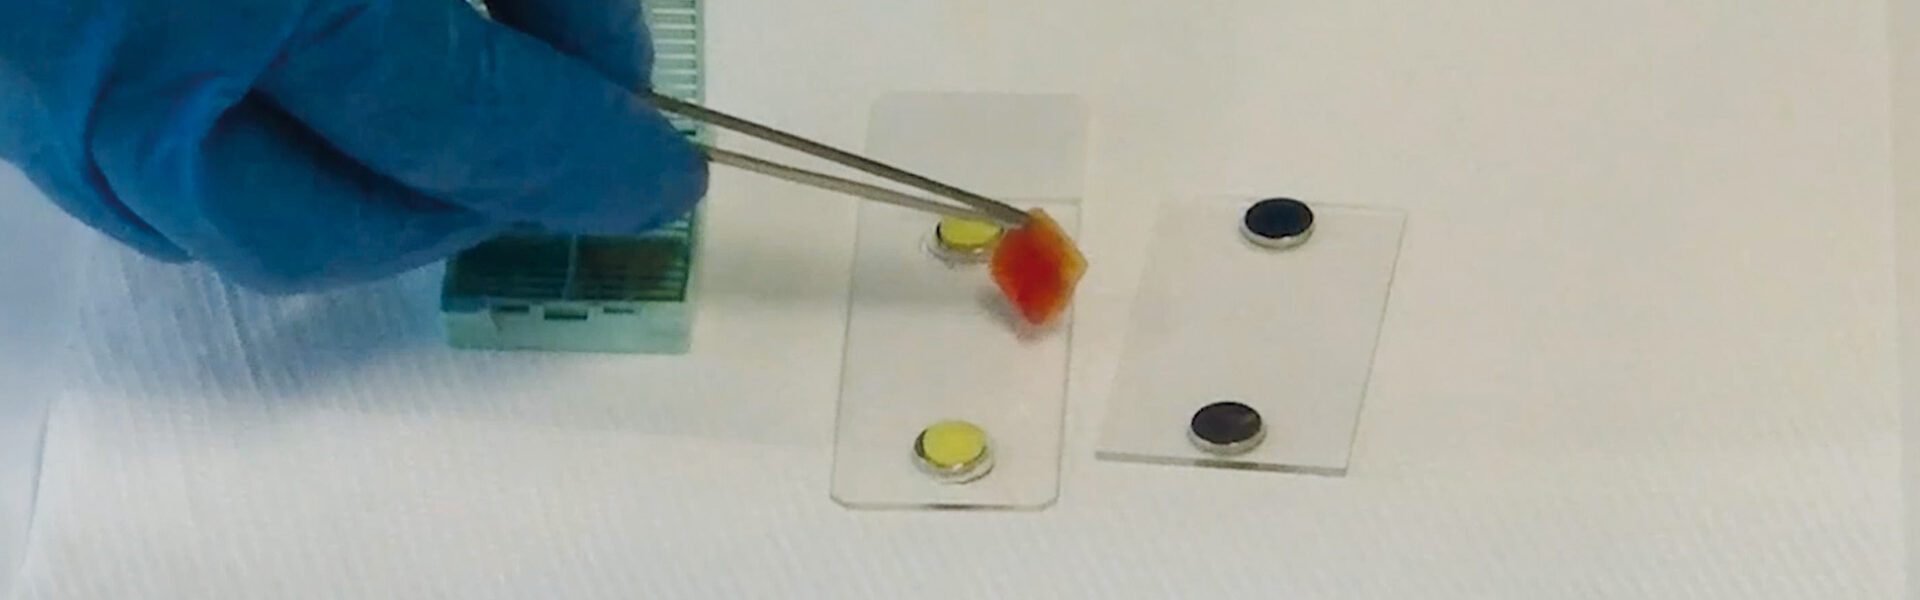

Step 1: Tissue Removal

The tissue is processed directly after excision without fixation.

Step 2: Staining Procedure

The specimen is then quickly and easily stained with a fluorescent dye and mounted on a glass slide.